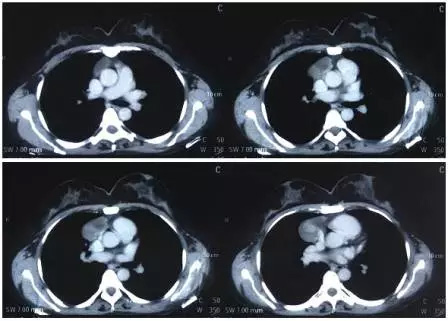

女性患者,45岁,因“查体发现前纵隔占位性病变4天”入院。查体:胸廓对称,胸壁无压痛及肿物,双肺呼吸音清,未及明显啰音。外院胸部强化CT示:心包右前方可见一占位性病变,不均匀强化,考虑畸胎瘤可能性大。病变较大,对周围脏器有一定压迫,良恶性不能确定,患者较年轻,手术指征明确,决定行胸腔镜纵隔肿瘤切除术。术前胸部CT如下图所示。